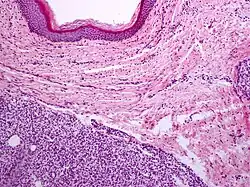

Capillary hemangioma

Strawberry naevus, H&E stain

A precise history of the growth characteristics of the IH can be very helpful in making the diagnosis. In the first 4 to 8 weeks of life, IHs grow rapidly with primarily volumetric rather than radial growth. This is usually followed by a period of slower growth that can last 6–9 months, with 80% of the growth completed by 3 months. Finally, IHs involute over a period of years.[36] The exceptions to these growth characteristics include minimally proliferative His, which do not substantially proliferate[35] and large, deep IHs in which noticeable growth starts later and lasts longer.[36] If the diagnosis is not clear based on physical examination and growth history (most often in deep hemangiomas with little cutaneous involvement), then either imaging or histopathology can help confirm the diagnosis.[33][37] On Doppler ultrasound, an IH in the proliferative phase appears as a high-flow, soft-tissue mass usually without direct arteriovenous shunting. On MRI, IHs show a well-circumscribed lesion with intermediate and increased signal intensity on T1- and T2-weighted sequences, respectively, and strong enhancement after gadolinium injections, with fast-flow vessels.[33] Tissue for diagnosis can be obtained via fine-needle aspiration, skin biopsy, or excisional biopsy.[38] Under the microscope, IHs are unencapsulated aggregates of closely packed, thin-walled capillaries, usually with endothelial lining. Blood-filled vessels are separated by scant connective tissue. Their lumina may be thrombosed and organized. Hemosiderin pigment deposition due to vessel rupture may be observed.[39] The GLUT-1 histochemical marker can be helpful in distinguishing IHs from other items on the differential diagnosis, such as vascular malformations.[34]